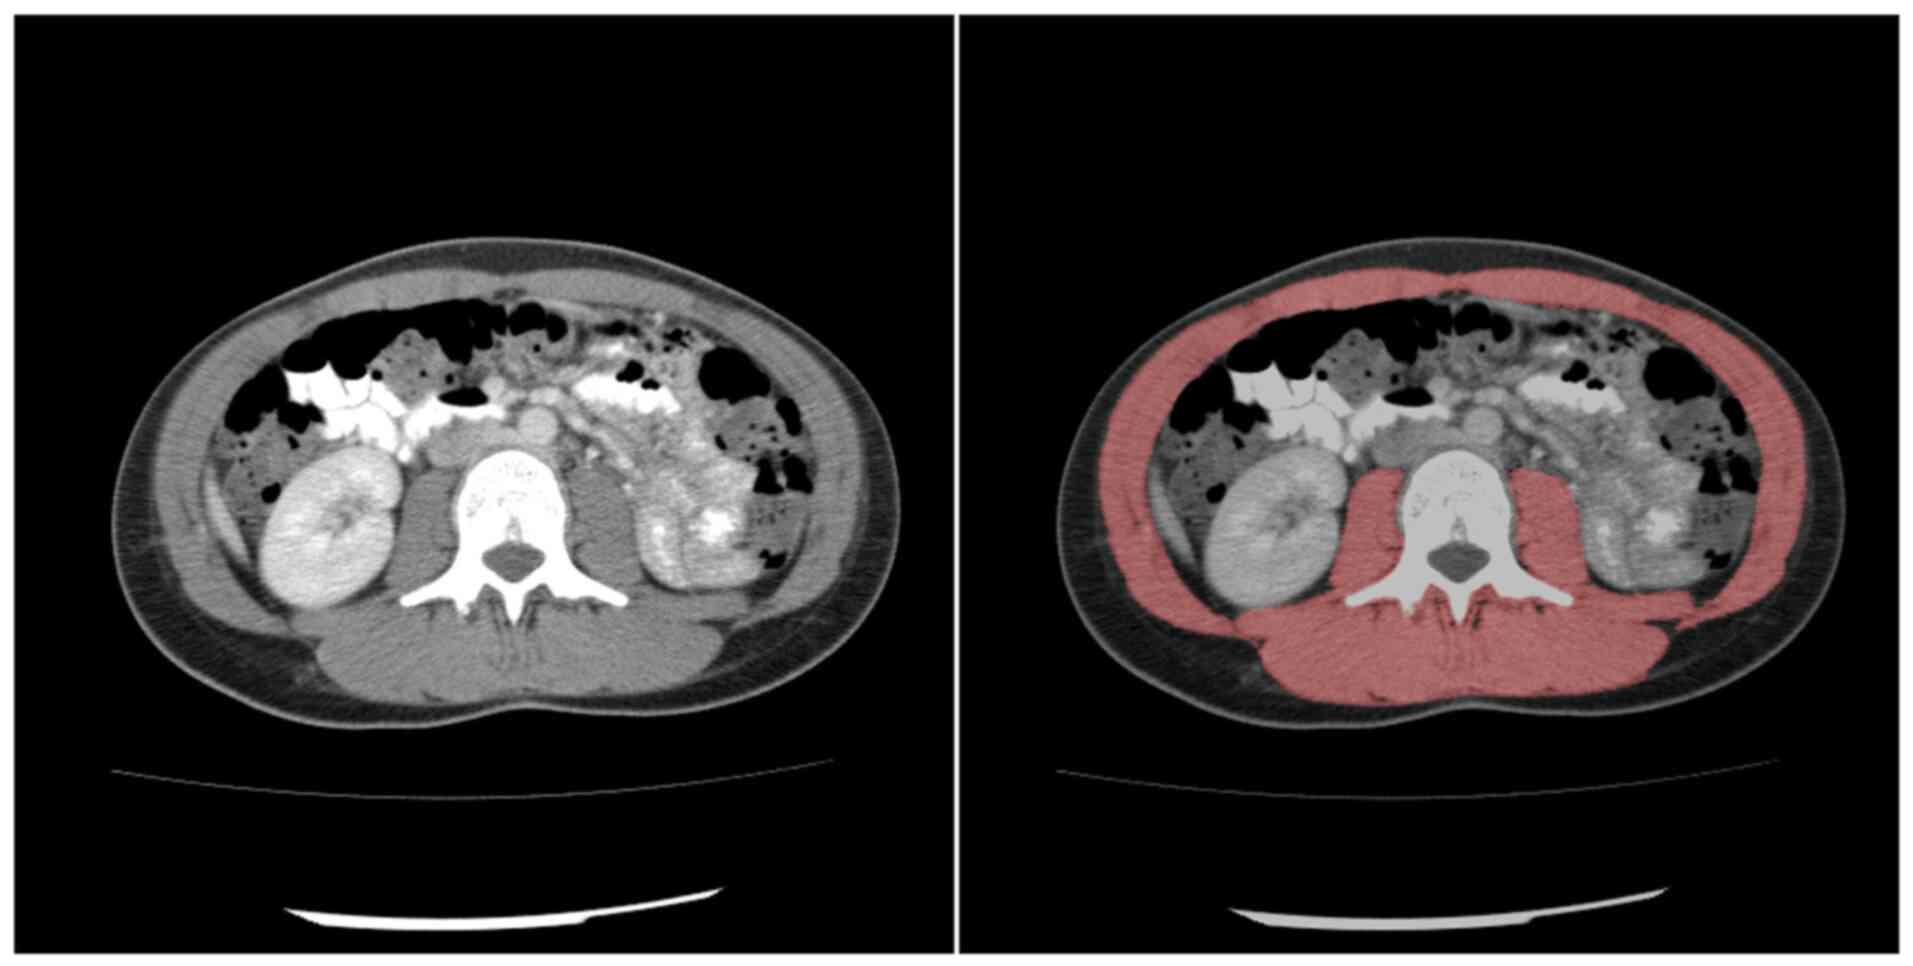

Low skeletal muscle mass as a proxy parameter for sarcopenia acts as a non‑invasive imaging marker that is associated with poor prognosis in numerous types of cancer. The present study aimed to assess the influence of body composition parameters on overall survival (OS) and progression free survival (PFS) in patients diagnosed with primary central nervous system lymphoma (PCNSL). A total of 98 patients with PCNSL treated at University Hospital Magdeburg (Magdeburg, Germany) from 2013‑2019 were retrospectively studied. Patients with a pre‑treatment staging computed tomography (CT) scan that included the third lumbar vertebra were reviewed for analysis. Skeletal muscle area (SMA), skeletal muscle index (SMI), mean muscle density and skeletal muscle gauge (SMG) were measured on the CT scan prior to treatment. Parameters were associated with OS and PFS. Overall, 72 patients were included in the present study. Results of the present study demonstrated that the median OS was 10 months (range, 1‑181 months), and 37 patients (51.4%) presented with sarcopenia. Moreover, the median OS was 7 months in the sarcopenic group and 32 months in the non‑sarcopenic group. Results of the present study further illustrated that SMI, SMA, density and SMG did not exert a significant effect on OS. Notably, the median PFS was 2.5 months in the low SMI group and 10 months in the normal SMI group. Body composition parameters did not exert a significant effect on PFS. Overall, the results of the present study demonstrated that sarcopenia was not a risk factor for decreased OS or PFS in patients with PCNSL undergoing systemic treatment.

View Figures

Figure 1

Figure 2